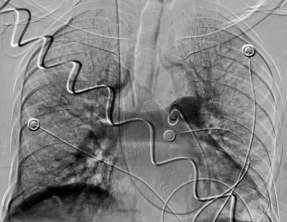

肺动脉左右分支大量血栓(左边血栓说明) 下腔静脉大范围血栓(滤器置入拦截)(右图血栓说明)

见此情形,放射介入专家小心翼翼操作,将滤器死死卡住血栓头,接下来就是第二步:完成肺动脉开通。重症医学科专家加大氧流量,血管活性药物稳定血压,为介入操作创造时间,同时介入专家猪尾巴导管上、导引导管上,不停进行各段抽吸、取栓,经过一个小时的精细操作,功夫不负有心人,双肺动脉干通了,主要肺动脉分支通了,肺血管网明显增多了,患者的情况也好转了起来!也就意味着第二步操作成功!随后的第三步,介入专家对下肢血栓进行了抽吸、取栓,并置入溶栓导管进行持续药物灌注溶栓。又经过两个小时,在两科的密切合作下,整台手术顺利完成。

手术完几个小时,当天下午就传来好消息,患者生命体征明显好转。在放置导管的第三天,患者再次来介入科造影,发现肺栓塞基本消失,下肢血栓明显消失,滤器继续卡住下腔血栓!经过多学科努力,通过综合介入各种手段,重症肺栓塞患者抢救成功!